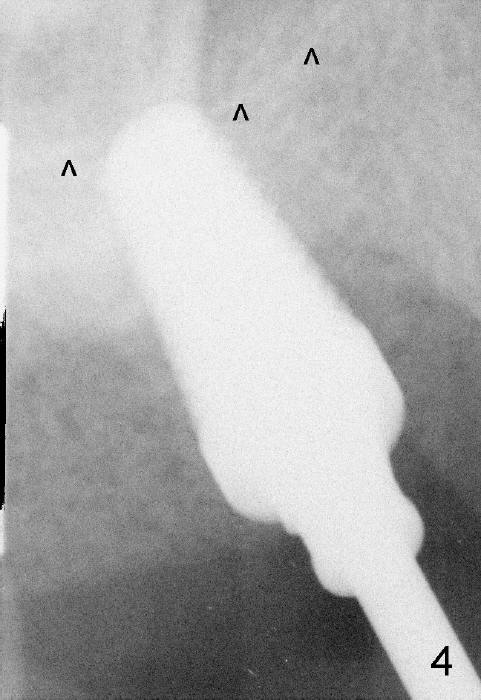

The upper right 1st molar fractures, the lingual portion mobile (Fig.1). There are deep pockets mesiolingually and distolingually. Fig.2 is preop PA, showing mesial bone resorption (*). The 84-year-old lady agrees extraction and immediate implant. Extraction is difficult due to not only root fracture but also hemorrhage. Following debridement of granulation tissue, the 3 sockets are packed with gauze for hemostasis. Even so, there is oozing from the bone. The septum can not be seen clearly. Its position is determined by an explorer. Osteotomes have to be used for osteotomy in the septum, followed by taps. The first intraop PA shows that 5x20 mm tap penetrates the sinus floor (Fig.3 ^). The osteotomy is further enlarged until 7x17 mm tap with stability (Fig.4). So far there has been no sign of sinus membrane perforation. Mixture of freeze dry mineralized bone and Osteogen is placed in the socket and pushed to the buccal and lingual walls as well as into sinus using a 4 mm flat end osteotome. A 7x17 mm implant is initially difficult to be inserted possibly due to blockage by bone graft. The osteotomy have to be recreated by a series of osteotomes and taps before placement of the 7x17 mm implant. It appears that the apical threads have been engaged into the sinus floor for primary stability (Fig.5). The insertion torque is 40 Ncm. According to our experience (1,2), this is not enough; finally the torque is increased to 60 Ncm by turning the implant more apically. The large implant obliterates the socket mesiodistally; the buccal and lingual gaps are filled with bone graft, followed by a collagen membrane (Fig.6 *) and suture. In order to protect the membrane, a short abutment is placed (A) and perio dressing (Fig.7*) is placed without occlusal interference. The abutment is removed 1 month postop, as the perio dressing has been dislodged. The patient returns for restoration 8 month postop. Bone regeneration occurs apparently in the coronal aspect of the implant (Fig.8), especially mesially (*, as compared to Fig.5). The gingiva-level implant is slightly subgingival mesially (Fig.9 M), probably due to high placement (compare to Fig.6). There is no bone resorption 6 months post crown (Fig.10 C) cementation.